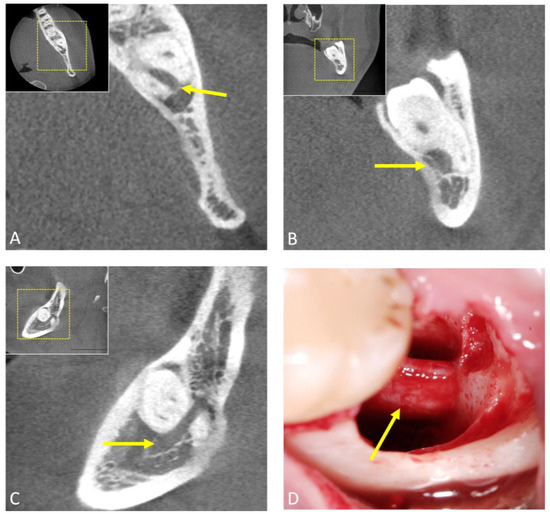

- Al-Haj Husain, A.; Stadlinger, B.; Winklhofer, S.; Müller, M.; Piccirelli, M.; Valdec, S. Mandibular Third Molar Surgery: Intraosseous Localization of the Inferior Alveolar Nerve Using 3D Double-Echo Steady-State MRI (3D-DESS). Diagnostics 2021, 11, 1245. [Google Scholar] [CrossRef] [PubMed]

- Al-Haj Husain, A.; Valdec, S.; Stadlinger, B.; Rucker, M.; Piccirelli, M.; Winklhofer, S. Preoperative visualization of the lingual nerve by 3D double-echo steady-state MRI in surgical third molar extraction treatment. Clin. Oral Investig. 2022, 26, 2043–2053. [Google Scholar] [CrossRef]